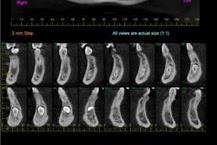

סיטי הדמיה דנטלית הוא מכון רנטגן שמבצע צילומי שיניים ולסתות. המכון פועל בפיקוח וברישיון מלא של משרד הבריאות וכולל שלושה סניפים - בראשון לציון, מודיעין וקריית ספר. אנחנו מתמחים בצילומיCT עבור שתלים ושינויים כלואות, צילומים אורתודנטים (יישור שיניים), צילומים פנורמיים, צילומי סטטוס ועוד. באמצעות מכשיר CT דנטלי הנחשב לחדיש בישראל ומכשור פנורמי דיגיטלי מתקדם, מובטחת האיכות הגבוהה ורמת הדיוק המרשימה של הצילומים שלנו. המכון מקיים הסדרים עם כמה מחברות הביטוח הגדולות והמובילות בישראל.